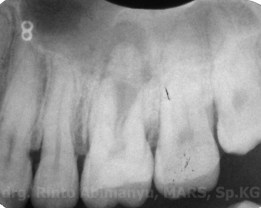

Pada saat diperiksa kondisi klinis terlihat gigi 26 masih ada tambalan komposit dan gingiva daerah bukal ada fistula.. Perkusi positif, palpasi positif dan tidak ada kegoyangan gigi.

Dari foto ronsen terlihat tambalan yang hampir mengenai kamar pulpa dan lesi radiolusen yang luas pada akar palatal…. Dari hasil pemeriksaan klinis dan radiografis sudah bisa dipastikan bahwa gigi ini nekrosis, dan perjalanan infeksinya sudah sampai membentuk abses…